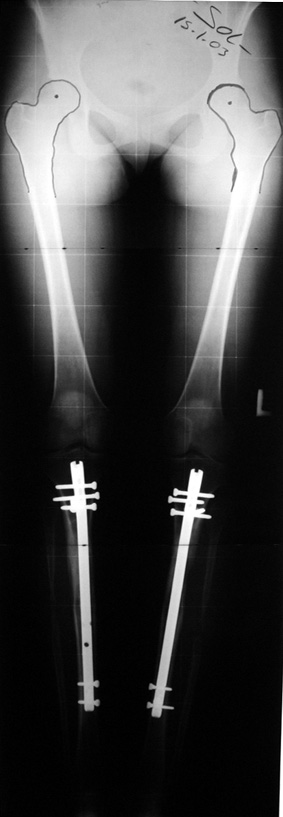

In selected cases, we prefer to use a combination of a unilateral dynamic axial fixator and an interlocked intramedullary nail, in order to protect the length and alignment after the completion of the lengthening procedure. As a prerequisite for this technique, the narowest diameter of the medullary cavity shall be wider than 7 mm and the length of the nail segment distal to the osteotomy site shall be at least 8 cm. after the completion of the lengthening procedure.The intramedullary nail neutralizes shear and bending forces on femur during lengthening, shortens external fixation time, and protects newly formed bone against fractures. In our series, subtrochanteric osteotomy was performed in one case. No varus angulation occured despite the intramedullary nail.

Ilizarov stressed the significance of endosteal blood circulation for distraction osteogenesis. Although we placed the intramedullary nail after reaming the femur in all cases, the time for callus formation was not longer than expected. Thus we found that there is no slowing in the rate of new bone formation due to disruption of medullary blood flow. The rationale of this finding is revascularization that occurs following reaming of the medullary cavity, the fixation stability with the intramedullary nail and early functional weight bearing. The potential disadvantages of a combined use of external and internal fixation metods are increased blood loss, intramedullary infection, risk of fat embolism and excessive metal load.The most fearsome complication is a deep intramedullary infection (panosteomyelitis) triggered by pin tract infection.No such complication was encountered in our series. In order to avoid this complication, after the completion of lengthening the nail shaill be interlocked from the medial side, and contact of internal and external fixator pins shall be avoided.

Another complication of lengthening over nail in children is development of secondary coxa valga due to damaging of greater trochanter, which is close to the entry site of the nail. All cases but one in our series were skeletally mature. One case was 12 years old, and no coxa valga deformity was detected at last control. The case is still under control.

The combination of intramedullary anil and dynamic axial external fixator is harder as a technique than Standard Ilizarov applications. However, it is stil appealing due to the following advantages: shortening of the duration of external fixation, protection against refracture, early rehabilitation, gaining maximum range of motion and daily quality of life. These advantages are more important than disadvantages such as increased cost, increased blood loss and potetntial deep infection. All in all, we believe that the technique of femoral lengthening over an intramedullary nail is a safe and reliable method and provides advantages over standard Ilizarov aplications.